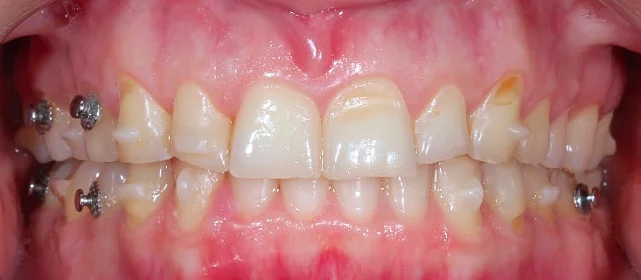

Верхняя челюсть выступала вперёд относительно нижней с обеих сторон (II класс по Энглю). Обе челюсти сужены, зубы стояли скученно. Нарушена кривая смыкания — жевательные зубы были на разной высоте. На двух передних зубах верхней челюсти ранее установлены металлокерамические коронки.

Прозрачные элайнеры Click на обе челюсти. Расширить зубные дуги, убрать скученность, исправить прикус и выровнять линию смыкания. Лечение с учётом имеющихся коронок. Основной набор — 31 капа. Срок — около 1,5 лет.

Проблема: Пациентку беспокоили неровные зубы и неправильный прикус. При осмотре нашли сразу несколько проблем: обе челюсти сужены, зубы стоят скученно, верхняя челюсть выступает вперёд (II класс по Энглю), кривая смыкания деформирована — жевательные зубы на разной высоте. На двух передних зубах верхней челюсти стояли старые металлокерамические коронки, которые нужно было учитывать при планировании.

Непростой случай: II класс, сужение, скученность, деформация кривой Шпее и металлокерамические коронки на 11 и 21. Коронки ограничивают варианты ретенции — на верхней челюсти вместо ретейнера используем капы. Это осознанное решение, принятое совместно с пациенткой. 64 капы за 20 месяцев — хороший темп для такого объёма. Основной набор сделал базу, дозаказы довели до нормы.